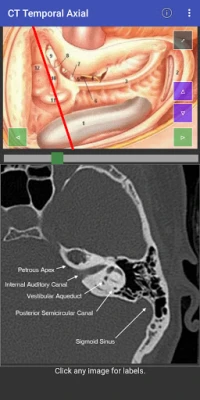

Domin sauƙaƙa fahimtar tsarin jikin ɗan adam ta hanyar hotunan CT scan, mun haɗa abubuwan ciki a matakai biyu (planes). Ɗaya daga ciki yana aiki a matsayin jagora (reference) wanda zai taimaka wajen fahimtar ɗayan sosai. Wannan hanya tana sa fahimtar tsarin jikin ya zama mai sauƙi da inganci, kamar yadda ake fuskanta a yanayin asibiti na gaskiya. Bugu da ƙari, za a iya gungurawa (scrolled) kowane mataki daban-daban, wanda hakan ke ba da damar fahimtar zurfin kowane sashi da cikakkun bayanansa cikin sauƙi.